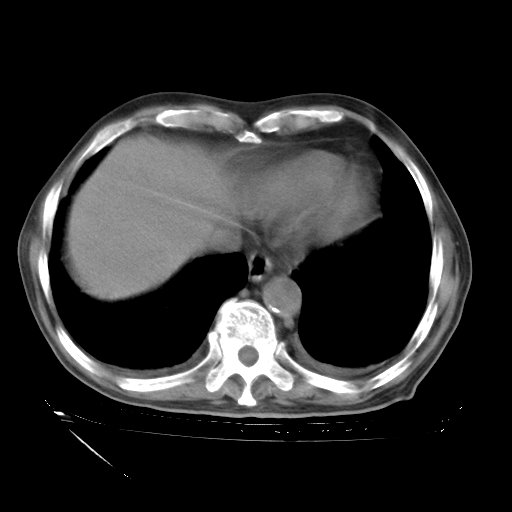

甲强龙80mg/日+抗结核治疗(异烟肼+利福霉素+乙胺丁醇)10天。复查肺部CT。

治疗10天肺部CT

经过24天治疗,岳父的病情基本稳定。生活基本可以自理,可以下床活动。呼吸困难早已消失。体温基本正常。

主要治疗甲强龙80mg×14天,60mg×10天;同时抗结核(异烟肼+利福平+乙胺丁醇)。环磷酰胺0.1 tid 10天。